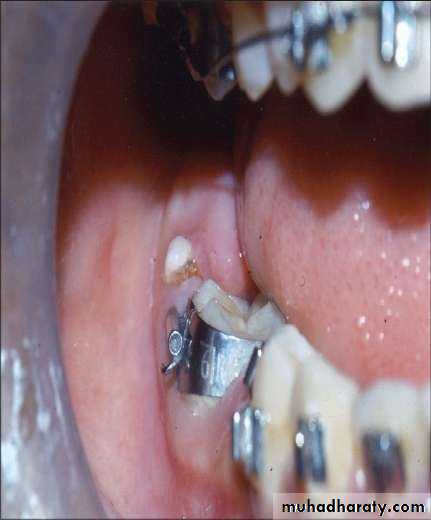

• Large lesion cause expansion of the jaw.• Most odontomas are asymptomatic.

• Odontomas may block the eruption of a permanent tooth .

• Erupted odontomas